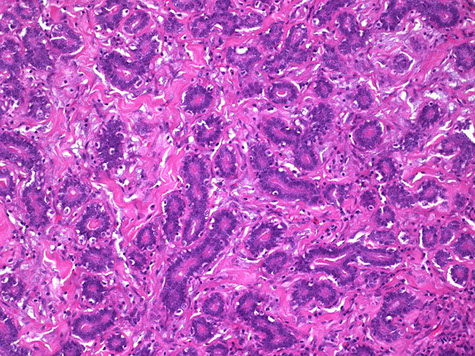

Micro: scattered oval glands c single-layer epithelium (no ME cells) with angulated (teardrop) dilated infiltrative tubules hat radiate outward and have snouts

- usually surrounded by desmoplasia

IHC: Usually ER/PR (+), HER2 negative (thus Luminal A), (+) ER/PR, EMA

- neg S100

- should have dropout of p63 and SMM (negative)